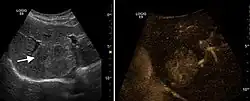

Liver cyst -

Hydatid liver cyst. Diagnostic criteria are the presence of membranes and sediment inside.